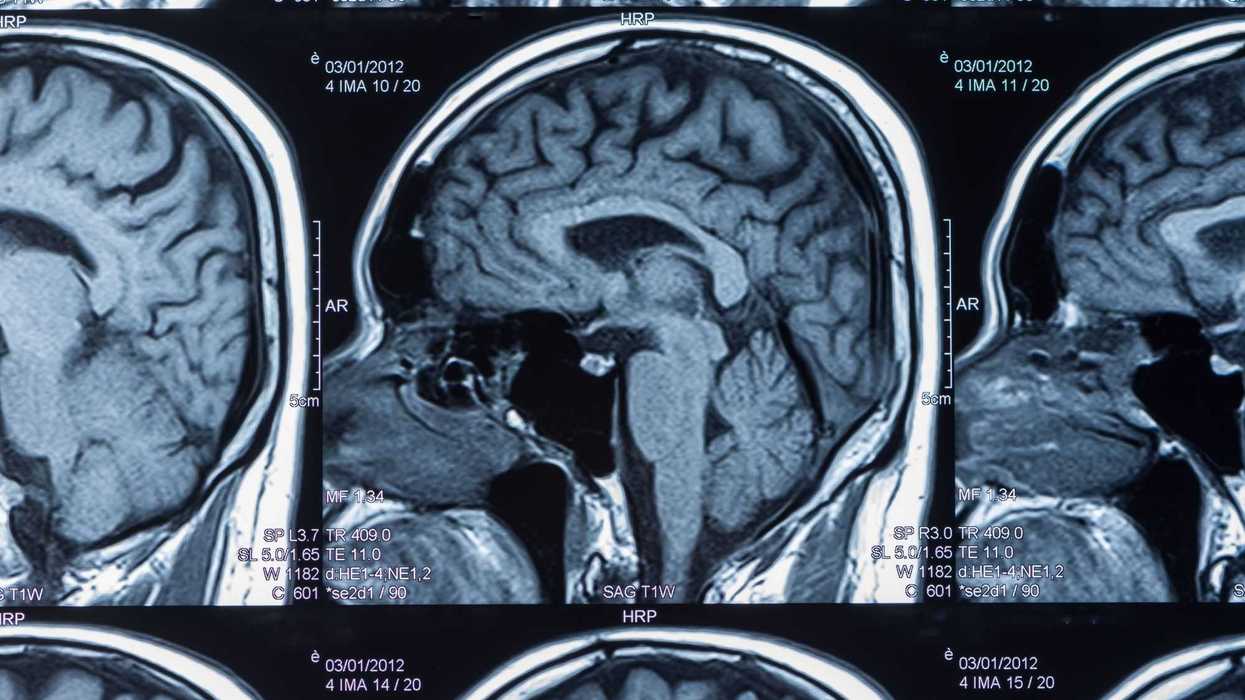

Donanemab es un anticuerpo inyectado por vía intravenosa que apunta a la acumulación de beta-amiloide, una proteína que se encuentra en el cerebro de muchos pacientes con Alzheimer, la forma más común de demencia.